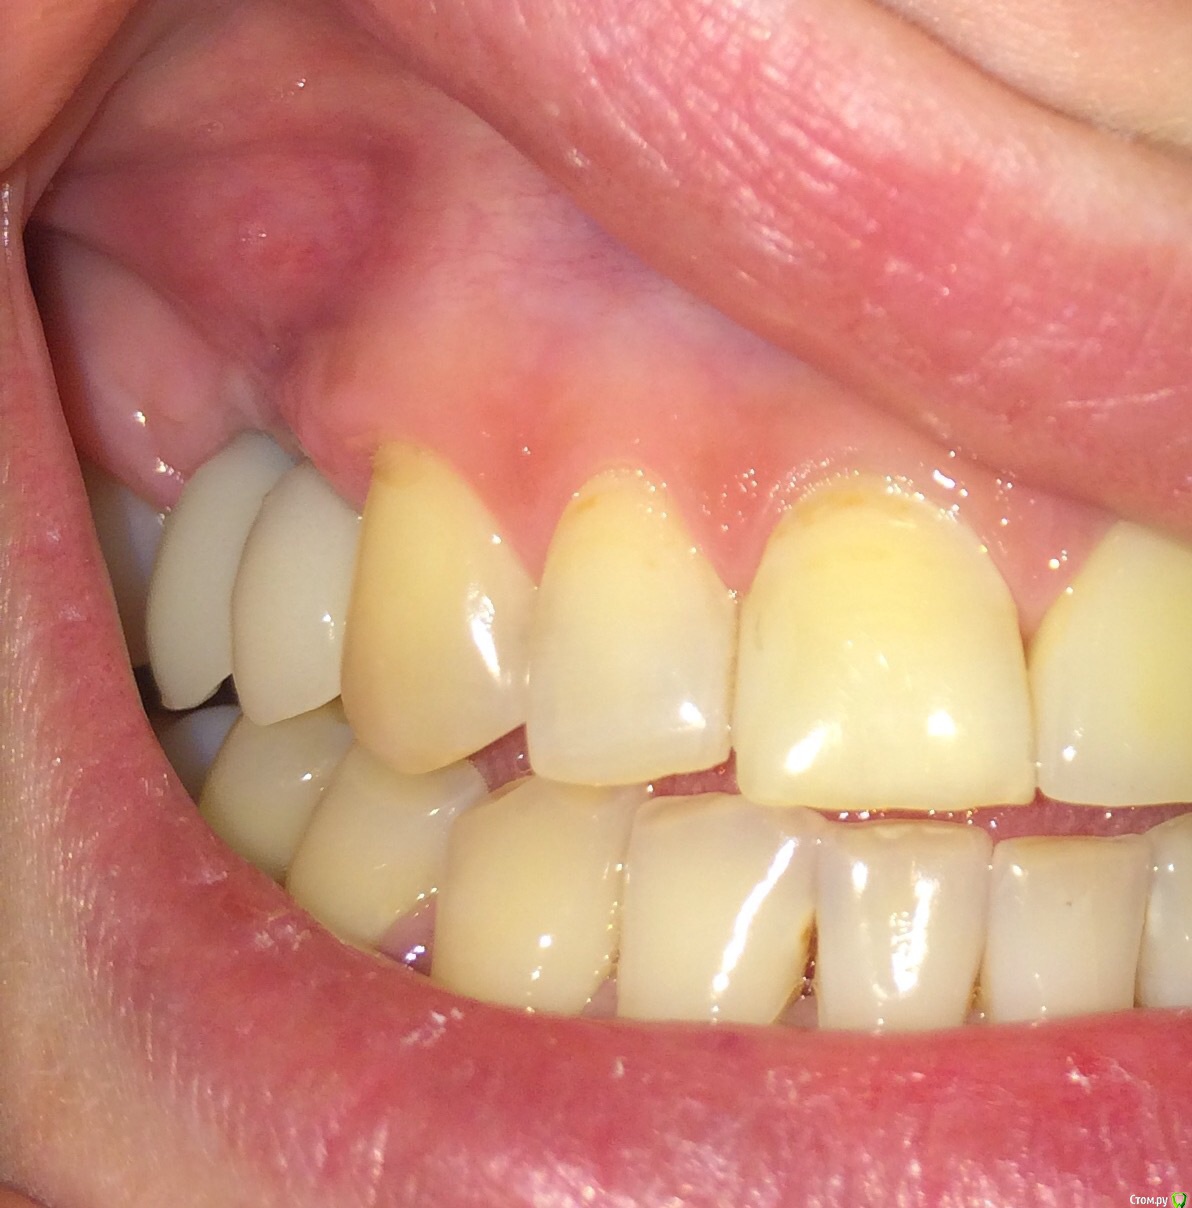

Nadiakroha Опубликовано 14 февраля, 2015 Автор Поделиться Опубликовано 14 февраля, 2015 (изменено) выкладываю фото, обвела пунктиром место наращенной десны. Извините, что столько времени у Вас отнимаю!Временные коронки стояли до операции по наращиванию, после заживления, через 10-12 дней поставили те же коронки, немного их подкорректировав, то есть сделали более естественную форму.. Вот фото коронок, до наращивания. Изменено 14 февраля, 2015 пользователем Nadiakroha Ссылка на комментарий

SDC Опубликовано 14 февраля, 2015 Поделиться Опубликовано 14 февраля, 2015 (изменено) выкладываю фото, обвела пунктиром место наращенной десны. Если так и есть, то это не тот регион, где необходимо увеличение объема.Трансплантированные ткани с бугра в.ч. действительно долго растут. И через год будет прирост, и через 2, но я сомневаюсь, что рост будет там, где нужно для эстетики. А зачем, в таком случае, снимали временные коронки? Насколько я вижу, трансплантация была на расстоянии от них? Изменено 14 февраля, 2015 пользователем SDC 1 Ссылка на комментарий

SDC Опубликовано 14 февраля, 2015 Поделиться Опубликовано 14 февраля, 2015 Временные коронки стояли до операции по наращиванию, после заживления, через 10-12 дней поставили те же коронки, немного их подкорректировав, то есть сделали более естественную форму.. Вот фото коронок, до наращивания.Значит Док планировал обойтись без мягкотканной пластики и решил провести ее позже? Ссылка на комментарий

Nadiakroha Опубликовано 15 февраля, 2015 Автор Поделиться Опубликовано 15 февраля, 2015 Доку вообще все понравилось, и его не смутили 2 "сросшихся" кривых зуба и я просила его исправить ситуацию, так как при улыбке у меня открываются боковые зубы больше,чем даже передние.. Спасибо, за честный ответ! вы подтвердили мои мысли о том,что операция была бесполезна, и что дело все в неправильно подобраном имплантате.. высылаю фото до удаления зуба,чтоб не быть голословной,и что у меня был нормальный сосочек (зуб 1,5 с металлокерамикой) Ссылка на комментарий